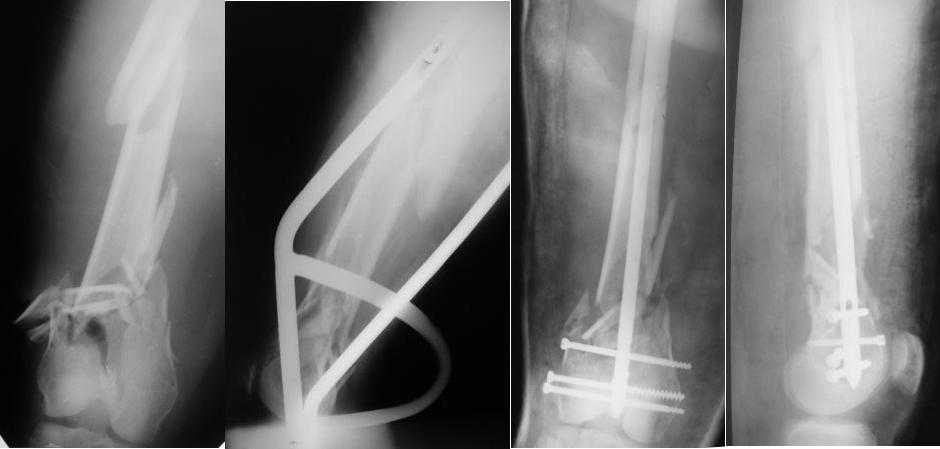

Псиологическки комфортно следовать вроде бы авторитетной догме (by even 1 mm, а то все пропало!), без оглядки на то, что догма эта не учитывает детали. В которых, как известно, дьявол.

Чтобы больной не смог сгибать колено, выстоять в сустав железо должно побольше значительно, чем на 1 мм. В приложении снимок с выстоянием ммм на 3, видна и функция колена. Хотя клиника импинджмента была, но даже не на один восклицательный знак. После удаления стержня проблемы и вовсе рассосались.

|